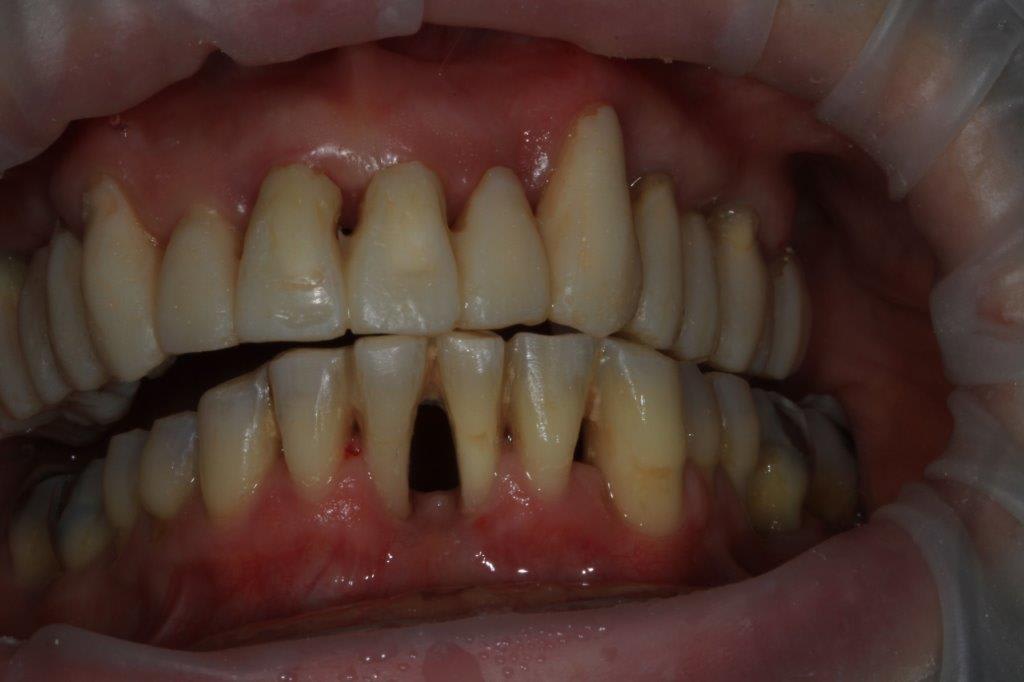

modèles de départ, photos avec le téléphone, désolé, mais ça donne une petite idée

--

xbk

La connaissance s'acquiert par l'expérience, tout le reste n'est que de l'information." ALBERT EINSTEIN